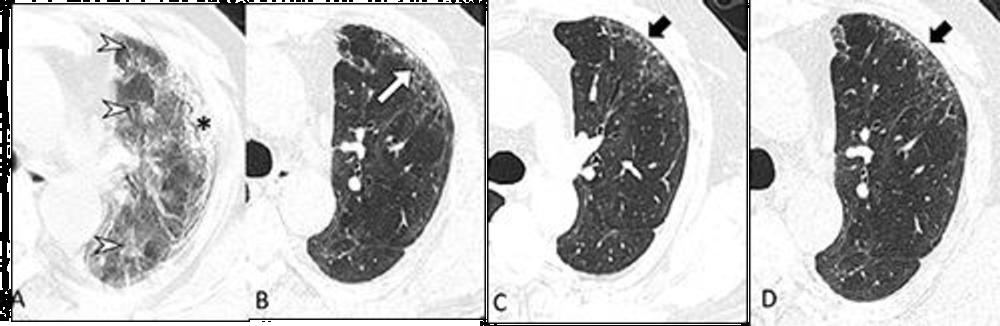

High-res (TIF) version

Figure 2. Serial transverse CT scans in a 65-year-old man with severe COVID-19. (A) CT scan obtained on day 23 after onset of symptoms showed diffuse ground-glass opacities (arrow heads) combined with subpleural consolidation (*) at the left upper lobe. (B) Image obtained at 6-month follow up showed subpleural primarily ground-glass opacity in the anterior upper lobe of the left lung along with minor bronchiectasis (white arrow). (C, D) Images obtained at 12-month and 2-year follow up showed presence of subtle, subpleural honeycombing at the same area (black arrows). This patient complained of ongoing exertional dyspnea and showed a mild diffusing capacity of the lung for carbon monoxide (74%) at 2-year follow up.